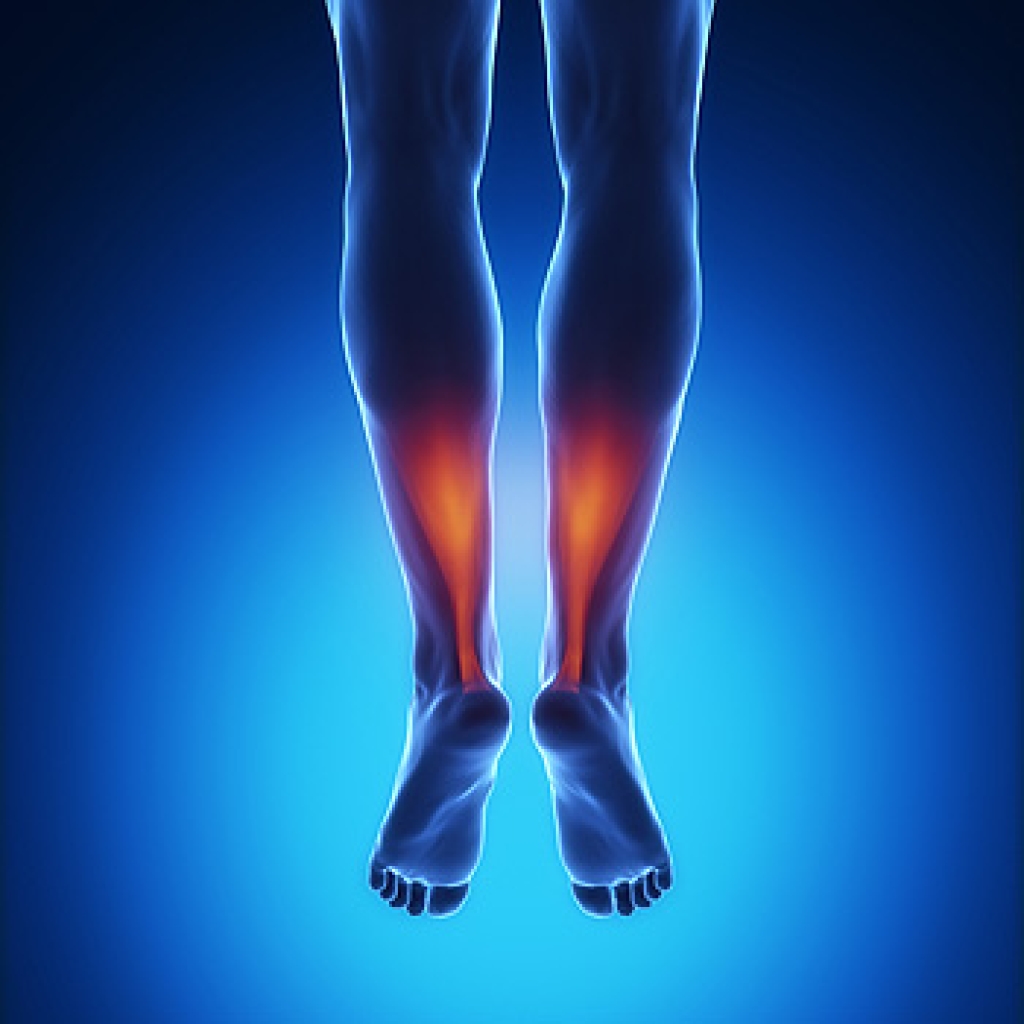

Many active people develop what is known as Achilles tendonitis, which occurs when the tendon becomes inflamed over a period of days, rather than suddenly. It is usually the result of repetitive use and the tightening of the calf muscles. A regular routine of stretching can help to strengthen the tendon and lengthen the muscles. Before starting any exercises, it may be wise to consult with a podiatrist who can examine the painful area and diagnose your injury properly. The calf is made up of two muscles, the gastrocnemius and the soleus, that the Achilles tendon connects to your heel. Both can be stretched using the same exercise in slightly different ways. Stand with both hands pressed against a wall, touch the toes of one foot to the wall with the knee bent. Place the leg to be stretched straight back, with the heel up and the leg straight. Be sure that the heel lines up with the foot. Slowly lower the heel. This should stretch the gastrocnemius (larger) calf muscle. Hold the stretch for a few seconds and repeat several times. To stretch the soleus muscle, do the same exercise with both legs bent. This releases the gastrocnemius and allows the smaller muscle to be stretched. If you are afflicted with an Achilles tendon injury, it is suggested that you schedule an appointment with a podiatrist.

The Achilles tendon is a tendon that connects the lower leg muscles and calf to the heel of the foot. It is the strongest tendon in the human body and is essential for making movement possible. Because this tendon is such an integral part of the body, any injuries to it can create immense difficulties and should immediately be presented to a doctor.

Achilles Tendinitis Symptoms

- Inflammation

- Dull to severe pain

- Increased blood flow to the tendon

- Thickening of the tendon